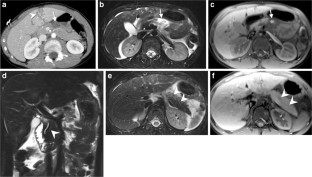

Of 3,265 patients presented as trauma team activations during the study period, only 28 (0.86%) children (19 boys, 9 girls; mean age: 7.14 years; age range: 1–15 years) had pancreatic injury. Of the available 27 CTs of the abdomen, 26 were performed on the day of trauma. Associated injuries were seen in 25/27 children, most frequently in the liver and lung, 16 (59.2%) each. There were 5 (19%) Grade I, 9 (33%) Grade II, 8 (30%) Grade III and 3 (11%) Grade IV. No patients had Grade V injury. No pancreatic parenchymal injury was identified in 2 (7%) patients with isolated fluid around the pancreas and mesentery. The pancreatic duct was visible in all 10 children (days: 0–330, median days: 41 post-trauma) who had MRI. Eight of these children, who had Grade III/IV injuries on CT and confirmed pancreatic duct injury on endoscopic retrograde cholangiopancreatography (ERCP) or surgery, showed either signal intensity difference in pancreatic parenchyma and/or caliber difference in the pancreatic duct proximal and distal to the injury site. Two patients died because of multiorgan injuries, 9 patients (mainly with Grade III and IV injuries) underwent surgery and/or ERCP, and 16 patients were managed conservatively. AAST grading of pancreatic injury on CT correlated with type of management (P=0.0001) with most of the Grade III and IV injuries treated with intervention and/or surgery while all of the Grade I and II injuries were treated conservatively.

Pancreatic injury is rare in children but often associated with other organ injuries most frequently involving the liver and lung. CT grading of injury correlates with management and guides intervention and/or surgery versus conservative treatment. MRI is useful for assessing pancreatic duct injury by demonstrating the pancreatic duct directly and/or secondary changes like signal intensity difference in pancreatic parenchyma and caliber difference in the pancreatic duct.

Fig. 4